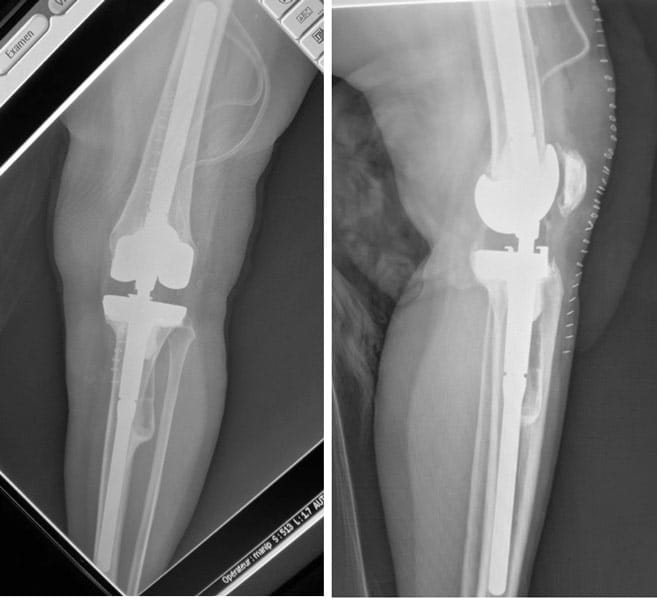

Homme 65 ans, Ostéotomie tibiale de valgisation il y a 15 ans.

Patient âgé de 75 ans, opéré par Prothèse uni-compartimentale interne il y a 3 ans.

Douleur et instabilité du genou du fait d’un descellement de la PUC ; reprise par Prothèse totale du genou postéro-stabilisée à glissement avec tige au tibia et reconstruction tibiale par cale interne.

Patient âgé de 80 ans ; opéré par Prothèse totale du genou il y a 5 ans. Douleur et instabilité. Déviation du genou de 13° ; pas de prothèse sur la rotule.

Pas d’infection.

Reprise par Prothèse totale du genou avec tiges fémorale et tibiale cimentées, semi-contrainte (séociété Zimmer, système LCCK), et bouton rotulien cimenté.